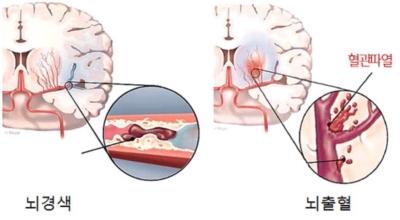

뇌 속에 혈액을 제공하는 혈관이 있는데, 이 혈관이 막히면 정상적으로 지급되어야 할 만큼의 혈액이 뇌까지 도달하지 못하여 뇌조직이 제 역할을 수행하지 못하는 것을 말해요. 이 시간이 지속될 경우 몸의 여러 곳에 지장이 생기며 이것을 뇌경색이라고 해요.

뇌경색의 주된 원인은 혈전입니다. 혈전이란 혈관 속에 피가 굳어진 덩어리를 얘기하는데 이것이 혈관을 막는 것이 뇌경색에 큰 영향을 준다고 해요. 평균적으로 많이 나타나는 연령대는 5~60대입니다. 뇌경색은 양쪽 뇌에 모두 생기는 것이 아니라 주로 한쪽 뇌에만 발생하지만, 주로 한쪽 팔다리가 마비되거나 얼굴 근육이 굳어버리기도 해요.

뇌경색이 생기는 원인은 아주 다양해요. 뇌경색은 뇌의 혈관이 막혀 뇌의 일부가 죽는 질병을 말하는데 주로 뇌경색의 원인은 혈전이며, 혈전으로 인해 뇌혈관이 막히는 위험 인자는 혈전을 발생하게 해요. 또한 동맥경화나 심장병, 혈관박리, 뇌혈관 기형 등으로 말미암아 생기게 될 수 있다고 하며 대부분이 60세 이상의 고령층에서 빈번히 나타나는 질환으로 알려져 있답니다.